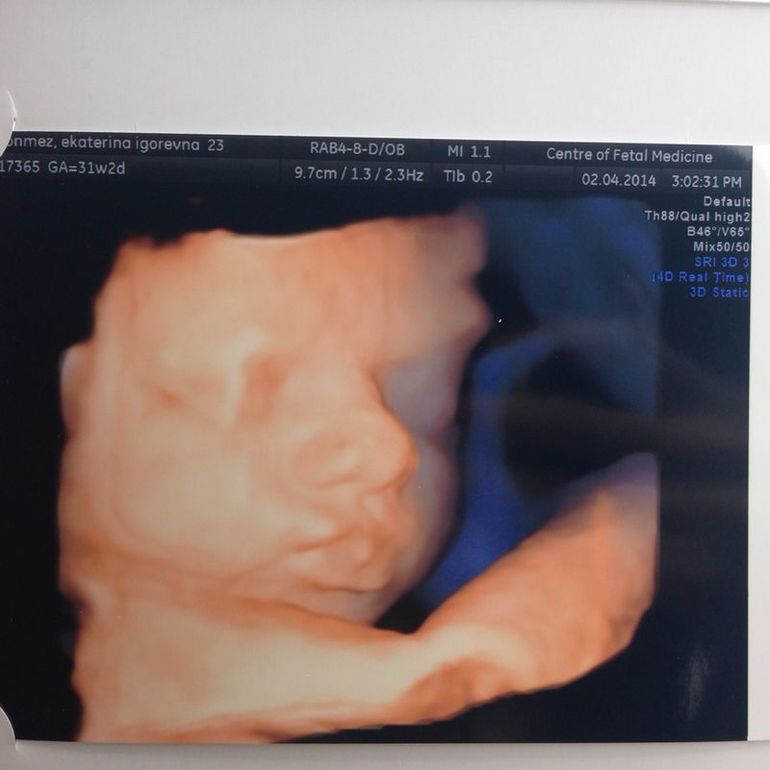

Третье УЗИ) ЦМП СПБ мини отзыв

сыночекСходили мы на третье узи 31 нед 2 дн в ЦМП. Все-таки в Отта мне больше понравилось.

тут на диск только меньше минуты почему-то записалось, т.е. не все обследование. а в Отта когда делали там прям 20 минут фильм) так хотела еще раз на пяточки его дома глянуть... ну ладно) Зато мы увидели нашего карапузьку

Лежит такой красивенький, губастенький)))) Губки как у папы, а вот надбровные дуги и нос видимо в мою породу.

УЗИст обрадовала: обвития нет, ни многоводия, ни маловодия - все идеально, плацента соответствует сроку. малыш весит 1527 (это не много?)

ПДР 2 июня.

не могу налюбоваться сама на него